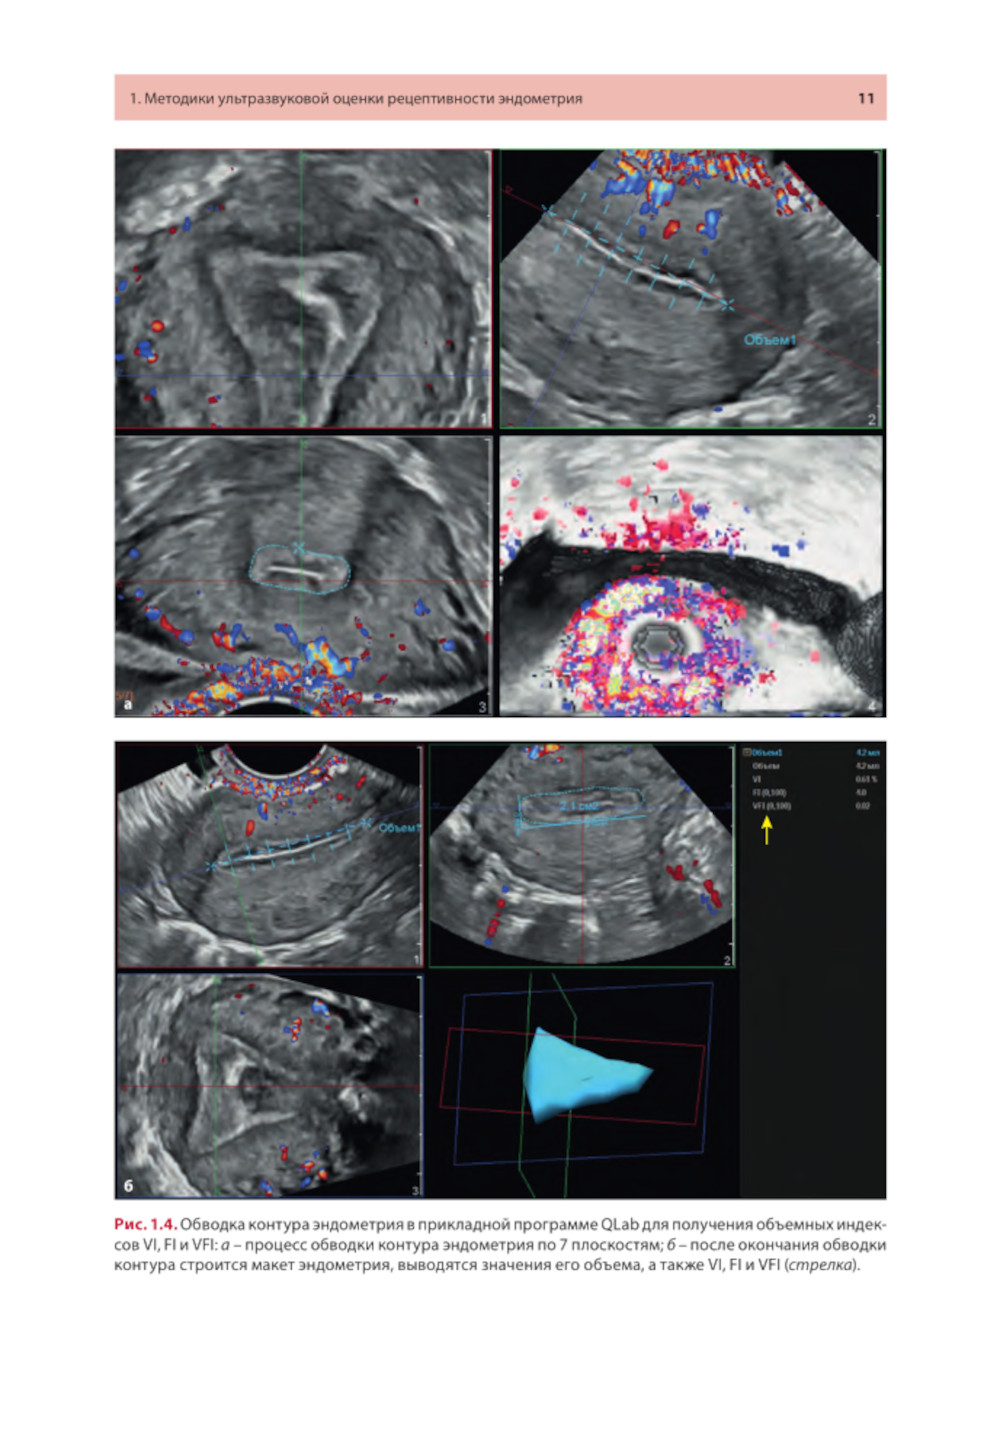

Методические рекомендации освещают современное состояние проблемы ультразвуковой оценки рецептивности эндометрия от общепринятых маркеров до малоизученных, в том числе перспективных, направлений. Описаны ультразвуковые методики, позволяющие оценивать признаки рецептивности в 2D- и 3D-режимах с акцентом на ошибках, которые влияют на интерпретацию результатов. Представлены различные шкалы комплексного анализа. Утверждено в качестве методических рекомендаций для проведения циклов тематического усовершенствования «Ультразвуковая диагностика в гинекологии», общего усовершенствования, ординаторов и аспирантов, проходящих обучение по направлению «Ультразвуковая диагностика, акушерство и гинекология, репродуктология». Протокол Ученого совета ФНМО МИ ФГАОУ ВО РУДН №5 от 16.05.2023.| Издательство | МЕДпресс-информ |